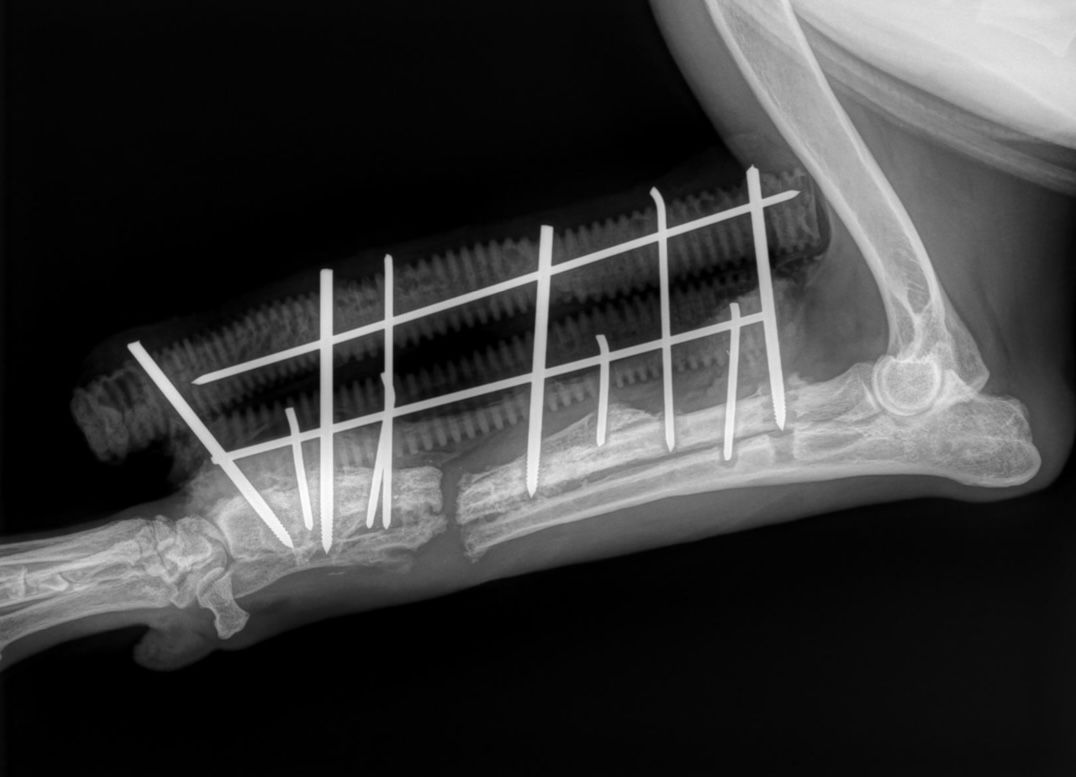

Der Knochen wurde nun auch an den Fixateur-Schrauben nekrös. Eine Kallusbildung am Bruchspalt nicht feststellbar.

Der Knochen sieht katastrophal aus (Siehe aktuelle Röntgenbilder):

Eine Amputation ist hochwahrscheinlich.

Aurelia musste operiert werden. Sie hatte zahlreiche Bissverletzungen und ihr rechter Unterarm wurde gebrochen, sowohl Elle als auch Speiche.